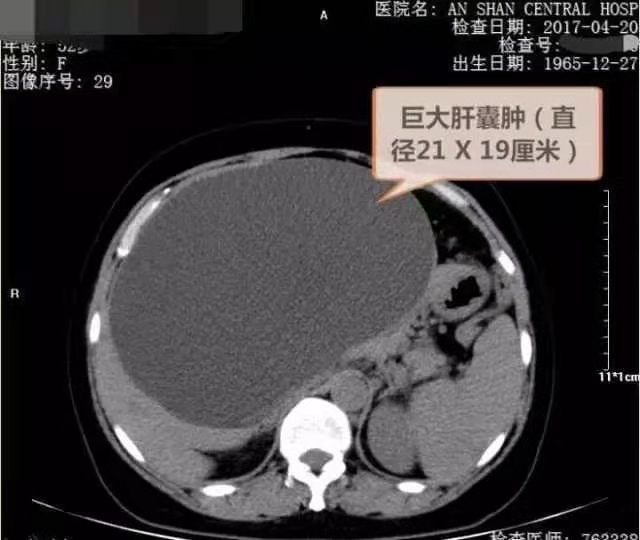

2)囊肿病因大多数系肝内小胆管发育障碍所致,单发性肝囊肿的发生是由于异位胆管造成。肝囊肿生长缓慢,所以可能长期或终生无症状,其临床表现也随囊肿位置、大小、数目以及有无压迫邻近器官和有无并发症而异。囊肿较小者一般无症状;囊肿增大后,可出现肝大、右上腹部不适、腹胀、腹部钝痛及腹部包块等症状。